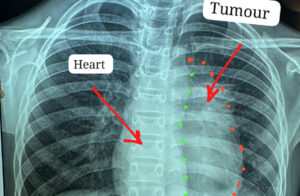

डॉक्टरों के अनुसार यह ट्यूमर सामान्यतः 40 से 60 वर्ष के लोगों में पाया जाता है और बच्चों में इसका मिलना अत्यंत दुर्लभ है। यह ट्यूमर हृदय, पेरिकार्डियम, फ्रेनिक नर्व महाधमनी (एओर्टा), मुख्य पल्मोनरी आर्टरी, लेफ्ट एट्रियम और फेफड़े से चिपका हुआ था। ऐसे मामलों में ट्यूमर को पूरी तरह निकाल पाना (आर-0 रिसेक्शन) लगभग असंभव माना जाता है, लेकिन अस्पताल में उपलब्ध हार्ट-लंग मशीन की मदद से यह संभव हो पाया।

मुख्य ट्यूमर के अलावा फेफड़े की प्लूरल कैविटी में फैले तीन अन्य सैटेलाइट ट्यूमर को भी सावधानीपूर्वक निकाला गया, ताकि भविष्य में कैंसर दोबारा फैलने की संभावना न रहे। निकाले गए ट्यूमर का आकार लगभग 12×8 सेंटीमीटर और वजन करीब 400 ग्राम था।

ऑपरेशन के दौरान किसी भी आपात स्थिति के लिए हार्ट-लंग मशीन तैयार रखी गई थी। लगभग चार घंटे चली सर्जरी के दौरान हार्ट की झिल्ली, फ्रेनिक नर्व तथा फेफड़े के कुछ हिस्से को भी निकालना पड़ा। साथ ही हार्ट के लेफ्ट एट्रियम को भी रिपेयर किया गया क्योंकि ट्यूमर लेफ्ट एट्रियम से चिपका हुआ था। इस दौरान मरीज को चार यूनिट रक्त की आवश्यकता पड़ी।

सर्जरी के बाद ट्यूमर के नमूने को बायोप्सी के लिए पैथोलॉजी विभागाध्यक्ष डॉ. राबिया परवीन सिद्दकी के पास भेजा गया, जहां जांच में इसे इनवेसिव थायमिक कार्सिनोमा (टाइप-बी थायमोमा, स्टेज-3) पाया गया। इसके बाद कैंसर विभाग द्वारा मरीज को 25 साइकिल रेडिएशन थेरेपी दी गई।